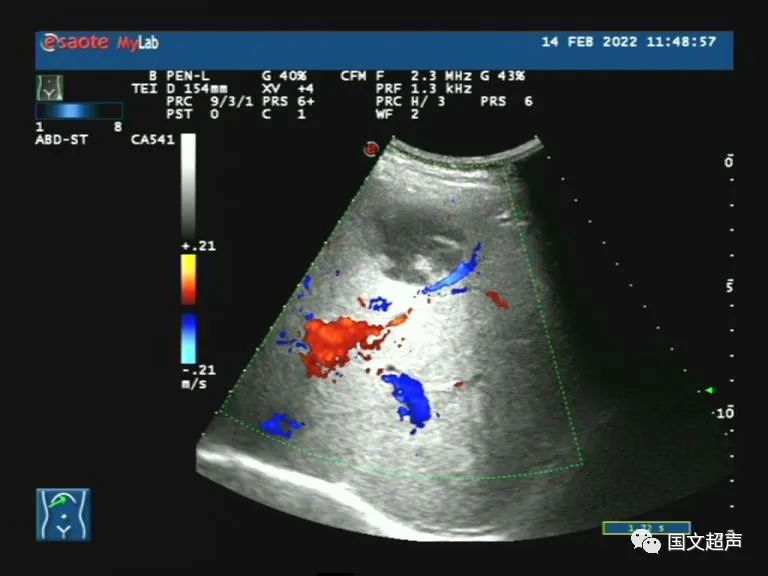

病例3:患者趙某,男,56歲,2天前于家中無明顯誘因突然出現(xiàn)腹痛,呈間斷性,伴納差,無腹瀉,發(fā)熱37.4°,自行口服藥物治療,癥狀未見明顯改善,為求進一步診治。

超聲檢查:肝右前葉下段探及混合回聲,形態(tài)尚規(guī)則,邊界較清晰,CDFI:血流信號不明顯。結合增強CT檢查結果,考慮肝膿腫,行抗感染及對癥治療。